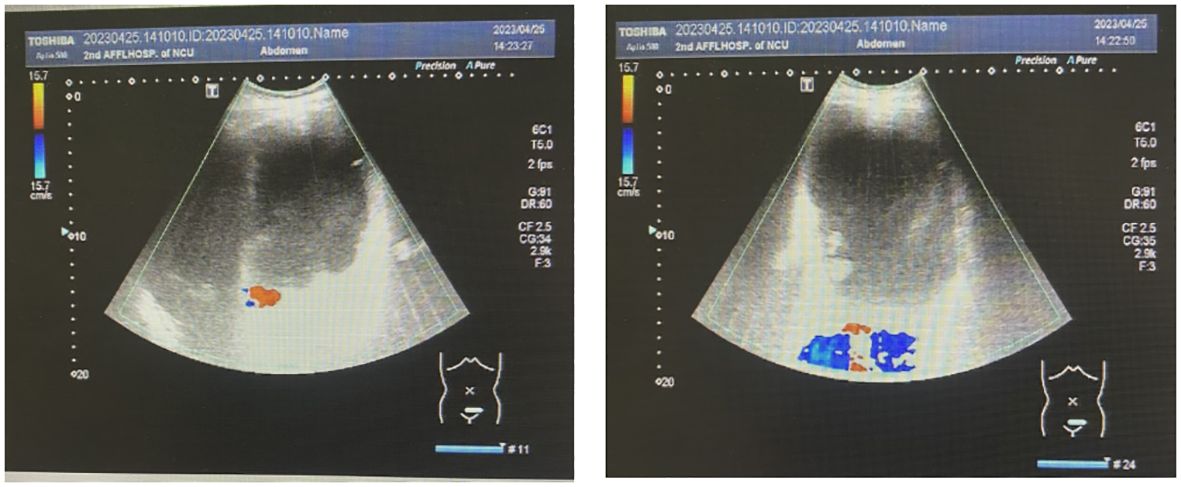

Fig 1. Gynecologic color ultrasonography suggested the presence of a serous cystadenoma originating from the right ovary. (Zhu, et al., 2024)